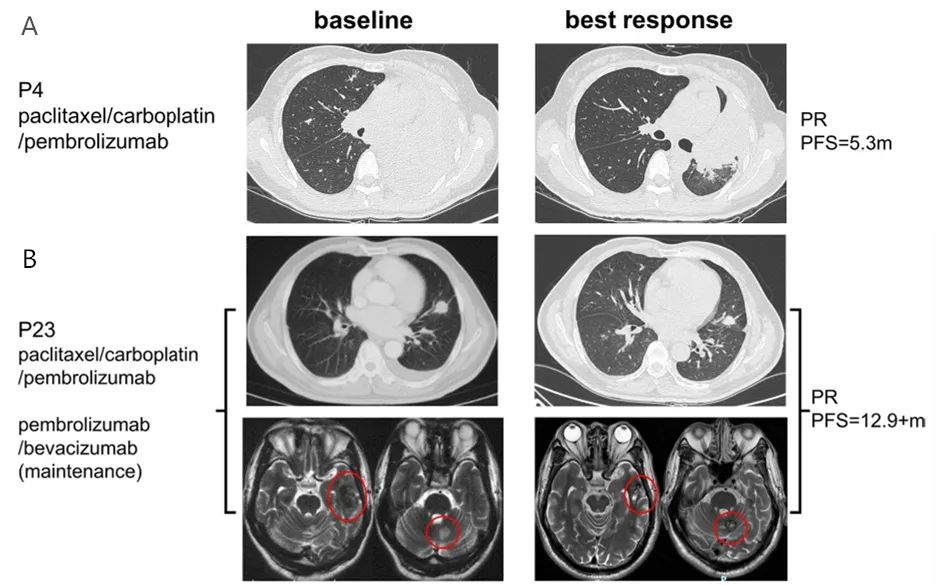

P4是一例携带RET重排的肺鳞状细胞癌患者,其PD-L1表达为15%。患者接受6周期化疗联合帕博丽珠单抗治疗,后续又接受2周期帕博丽珠单药治疗,最佳疗效为PR,PFS为5.3个月(图4A)。

P23患者携带KIF5B-RET重排,PD-L1表达为80%。患者接受4周期化疗联合帕博丽珠单抗治疗,后续接受帕博丽珠单抗和贝伐珠单抗联合治疗,最佳疗效为PR,肿瘤皱缩达到46%(图4B)。

图4. RET重排患者免疫治疗前后影像学变化